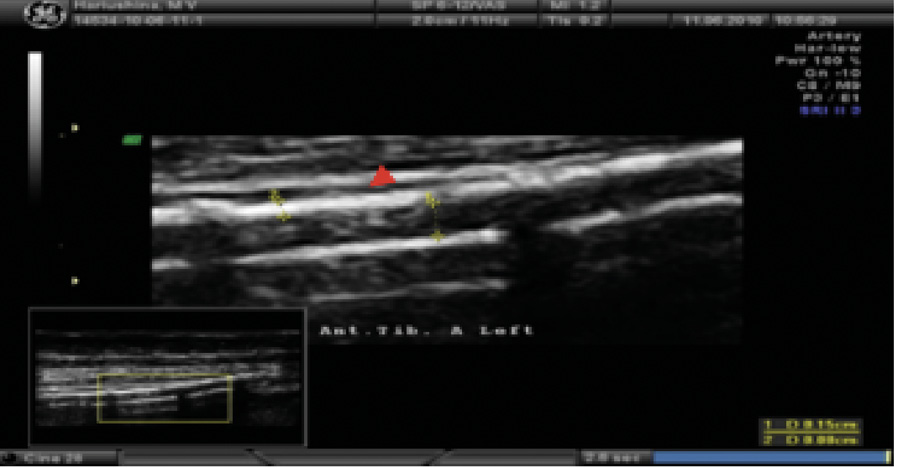

При измерении лодыжечно-плечевого индекса (ЛПИ) доплеровский сигнал не исчезал даже в случае нагнетания давления в манжете более 300 мм рт. ст. по трем измеряемым артериям. По левой окклюзированной в проксимальном сегменте задней большеберцовой артерии получен показатель 1,3, что отражает значимую кальцификацию сосудистой стенки. Распространение кальциноза наблюдалось и на пальцевые артерии, что сопровождалось несжимаемостью этих артерий, свойственной пациентам с ХБП, получающим заместительную почечную терапию, или пациентам после трансплантации почки. По данным ультразвукового дуплексного сканирования внечерепных отделов брахиоцефальных артерий, в устье левой внутренней сонной артерии выявлена кальцинированная атеросклеротическая бляшка (стеноз 20%). Ультразвуковое дуплексное сканирование артериовенозной фистулы левой верхней конечности: эхографические признаки кальциноза (рис. 5) с симптомами ускоренного кровотока в бассейне левой плечевой артерии (230 см/с) в сравнении с контрлатеральной плечевой артерией (77 см/с). Избыточное шунтирование артериальной крови по фистуле напрямую в венозное русло, предположительно, может способствовать развитию ригидности сосудистой стенки, что обусловлено изменением кинетических характеристик движущейся крови (давления, объема, скорости), иными словами, «напряжением сдвига». Вследствие повышенного воздействия на механорецепторы эндотелия могут активироваться патологические процессы, направленные на активацию сосудистой кальцификации у нашего пациента.

Рис. 5. Эхограмма пациента Т. Ультразвуковое дуплексное сканирование артериовенозной фистулы левой верхней конечности. Обызвествление стенок плечевой артерии артериовенозной фистулы левой верхней конечности (указано стрелкой)

При оценке состояния периферического кровотока у нашего пациента выявлены признаки выраженного кальциноза сосудистой стенки нескольких сосудистых бассейнов. В настоящее время полагают, что одним из ведущих факторов в развитии медиакальциноза может быть дистальная диабетическая полинейропатия [27]. Результаты нашего исследования указывают на развитие тяжелой периферической нейропатии, прогрессирование которой привело к формированию ДНОАП и необратимым поражениям костей стопы. По данным рентгенографии и ультразвукового исследования у больного отмечен выраженный кальциноз артерий голени и стопы, что характерно для пациентов с тяжелой дистальной нейропатией, хронической почечной недостаточностью и поражением артерий нижних конечностей. Наше наблюдение коррелирует с результатами отечественных и зарубежных гистоморфологических исследований материалов ампутированных конечностей у больных СД, описывающих преимущественно неатеросклеротическое утолщение интимы и кальциноз медиального слоя артерий, иногда в сочетании с тромбозом [28, 29]. Заключения полученных нами визуализирующих методов исследования подтверждают имеющиеся в литературе данные о связи между тяжестью дистальной диабетической нейропатии и выраженностью кальциноза артерий дистальных отделов нижних конечностей [30–32]. Абсолютная ригидность артерий голеней и стоп у пациента не позволила провести измерение систолического давления и расчет ЛПИ проходимых сосудов. В постокклюзионном сегменте одной из берцовых артерий данный показатель был значительно выше ожидаемого (< 0,9). Завышенный уровень систолического давления и несжимаемость дистального артериального русла нижних конечностей ассоциировались с высоким индексом коронарного кальция и высоким сердечно-сосудистым риском, что было ранее установлено в отечественных и зарубежных исследованиях [30, 33–35]. Помимо сенсорной нейропатии у нашего пациента важную роль в развитии медиакальциноза периферических артерий сыграла автономная нейропатия, о чем свидетельствует наличие ДНОАП, в патогенезе которой имеет место сосудистая десимпатизация [4]. При проведении ультразвукового исследования была визуализирована функционирующая кальцинированная артериовенозная фистула, что сопровождалось асимметричным повышением систолического АД в плечевой артерии на 20 мм рт. ст. и существенным увеличением скорости кровотока в сравнении с контрлатеральной плечевой артерией. Общепризнано, что повышение напряжения сдвига, например, при артериальной гипертензии, оказывает проатерогенное влияние на артериальную стенку [36]. При этом происходят пролиферация и изменение фенотипа эндотелиальных клеток с развитием атером, содержащих соли кальция и липиды [37]. Полученный нами результат ультразвукового исследования, указывающий на кальциноз артериовенозной фистулы, согласуется с данными литературы о том, что морфологический состав стенки фистулы может соответствовать описываемой эхографической картине. Так, гистологическая характеристика неоинтимальных гиперпластических поражений в условиях нарушенного напряжения сдвига может существенно отличаться от атеросклеротических поражений и состоит в основном из высокопролиферирующих гладкомышечных клеток сосудов, миофибробластов, неососудов и воспалительных клеток [38, 39]. При индукции механическим стрессом микроРНК, играющих патофизиологическую роль во внутриклеточной коммуникации и сигнальной системе гладкомышечных клеток сосудов, происходит их фенотипическая трансформация в остеобласты, что приводит к кальцификации сосудов [40, 41].